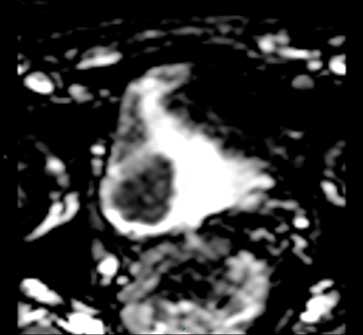

Hình 3a. Hình ảnh DWI trên cùng một bệnh nhân như Hình 2 cho thấy khối u có tín hiệu cao.

Hình 3b. Hình bản đồ ADC cho thấy sự khuếch tán hạn chế trong khối u

Hình ảnh cộng hưởng từ khuếch tán dựa vào tính chất khuếch tán của proton trong nước. Hình ảnh khuếch tán thu được khi sử dụng nhiều giá trị B (multiple B-value), khối u sẽ có tín hiệu cao trong hình ảnh nhiều giá trị B và thể hiện tín hiệu kém khi phản hồi qua bản đồ giá trị hệ số khuếch tán biểu kiến (ADC) (hình 3a và 3b). Bản đồ ADC phản ánh sự di chuyển của các phân tử nước và có mặt của sự tưới máu và khuếch tán mao dẫn. Những hình ảnh này sẽ được đánh giá khi kết hợp với hình ảnh T2 với cùng một mức độ.